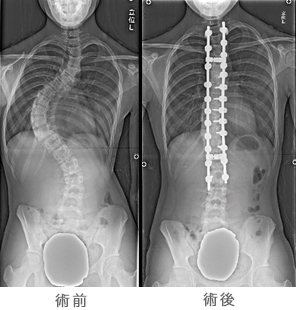

脊柱側弯症に対する矯正手術

側弯症の大部分は学童期の後半から思春期に発生します。側弯症では脊柱が横(側方)に曲がり、進行すると変形による心理的ストレスの原因や腰痛や背部痛、肺活量の低下などの呼吸機能障害、まれに神経障害を伴うことがあります。手術は曲がった脊柱を矯正固定する方法が行われます。背中から行う方法(後方法)と体の横から行う方法(前方法)があり、患者さんの年齢、側弯の部位、大きさ、タイプなどを考えて、いずれかあるいは両者が行われます。和歌山県立医科大学整形外科では、手術に伴う神経麻痺を防ぐための脊髄機能モニタリングや自己血輸血を導入することで手術の安全性を高めています。手術方法により異なりますが、概ね1週以内に装具を装着することなく歩行ができ、2−3週以内で退院可能となります。脊柱側弯症についてさらなる詳しい知識を望まれるかたは日本側彎症学会ホームページもご参照下さい。